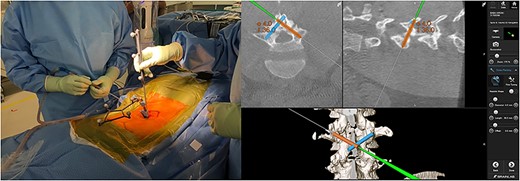

Skin incisions for screw insertion were made bilaterally (each 10 mm in length). The fascia and paravertebral muscles were cut for screw insertion. The screw insertion point, insertion angle, and screw length were planned using the navigation pointer and were registered in the navigation system (Fig. 2). The robotic arm was moved manually to a position near the target point, and it then automatically moved to the planned point precisely. The canula was inserted though the robotic arm, and the screw trajectory was made using a power drill (Fig. 3). After drilling, the guidewire was inserted into the drilled hole and tapping was performed through the guidewire. Finally, the planned screws were inserted via the guidewire. The screw position was confirmed by fluoroscopy and postoperative X-ray. Each wound was washed and closed without a drain tube (Fig. 4). There were no intraoperative complications.

Making screw hole using a power drill with robotic arm (left panel); insertion of screw via a guidewire (right panel).